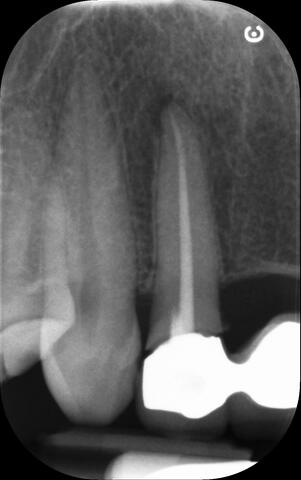

I am pleased to take endodontic referrals. Curved canals >30 degrees and potentially greater than 50 degrees can be negotiated. Sclerosed canals accessed. Post spaces prepared and the patient returned to you ready to restore.In most cases existing crowns, bridges and veneers can be retained with the endodontic access aesthetically restored after the full canal network has been treated.In the first instance I would prefer a radiograph and a brief list of patient expectations and a tooth history.

I really enjoy undertaking root canal treatments - rising to the challenge and helping people out of dental pain for the long term.I was privileged to be asked to speak at the 2016 BDA Conference, where I have a lecture about providing quality endodontic outcomes to patients, working as a generalist. Avoiding problems and pitfalls and maximising efficiency. One of the main matters that he covered was understanding that what is seen on plane radiography is utterly misleading and should not be the criteria by which a generalist continues treatment once it has been started.

At the 2016 BDA Conference, Thomas spoke about providing quality endodontic outcomes to patients, working as a generalist. Avoiding problems and pitfalls and maximising efficiency. One of the main matters that he covered was understanding that what is seen on plane radiography is utterly misleading and should not be the criteria by which a generalist continues treatment once it has been

started.